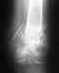

Добрый день, в январе делали остеосинтез лодыжки, в апреле сняли винт скрепляющий малую и большую берцовую кости. МБЦ не срослась к тому времени.Сейчас вот такая картинка. Имеет смысл снимать металл, или, можно его оставить?